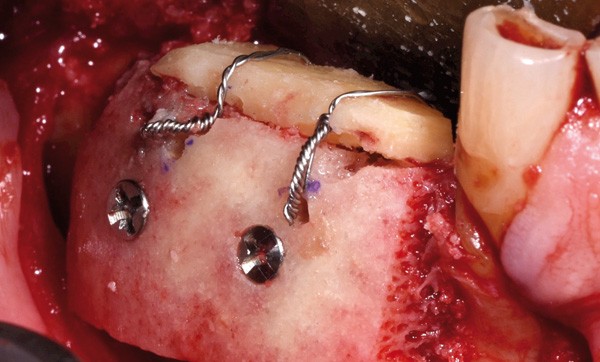

Allogreffes et reconstructions de crête à but préimplantaire

Nous avons étudié 100 greffes d’origine allogénique à but préimplantaire réalisées au cours des trois dernières années et nous avons comparé le taux de réussite de cette chirurgie implantaire par rapport à 100 greffes d’origine pariétale réalisées à la même période selon les mêmes protocoles chirurgicaux et avec le même opérateur.

Nous avons subdivisé les reconstructions de crête osseuse en fonction de leur importance quantitative et de la localisation de l’augmentation osseuse : transversale ou verticale (la quantification de l’importance de la greffe a été notée en phase peropératoire) :

– greffes transversales…